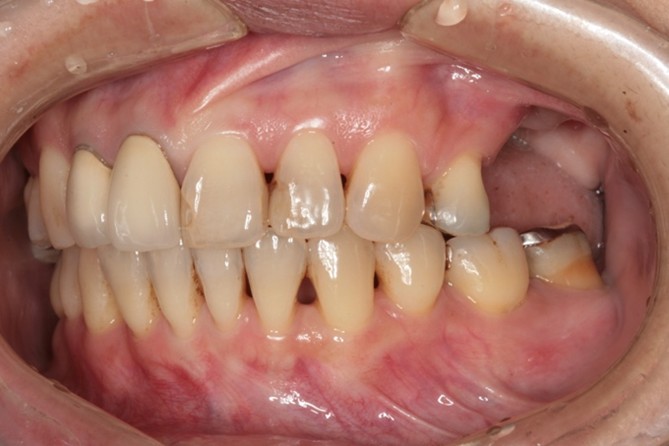

| 年代 | 61歳 |

|---|---|

| 性別 | 男性 |

| 治療内容 | 上顎部分床義歯、下顎全部床義歯で咀嚼障害。高度の骨吸収(インプラント困難な症例) 上額のオールオン6インプラント治療。下顎インプラントオーバーデンチャーによる治療。 レントゲン診断、CT診断、補綴シミュレーション、血液検査、心電図、CT撮影ステント製作、サージカルガイド製作、治療用義歯、静脈内鎮静法抜歯、骨造成手術、サイナスリフト(上顎洞底挙上術)インプラント埋入、骨の治癒期間(4ヶ月)、静脈内鎮静法、2次手術、印象・咬合採得、インプラント上部構造装着、義歯装着、メインテナンス |

| 治療期間 | |

| リスク | 術中の不可抗力によるトラブル(出血など)、術後注意事項を守らないことによる疼痛、感染、上部構造装着後口腔内清掃を怠ったことによるインプラント周囲組織の炎症 |

| 副作用 | 治療後の口腔内清掃、及びメインテナンスを怠ったことによるインプラント周囲粘膜炎またはインプラント周囲炎 |

| 費用 | 4,400,000円(税込) (CT撮影診断、血液検査、心電図モニター、補綴シュミュレーション、治療用義歯、サージカルガイド製作、静脈内鎮静法、インプラント埋入、骨造成手術、サイナスリフト(上顎洞底挙上術)投薬、2次手術、印象・咬合採得、インプラント上部構造などを含む) |